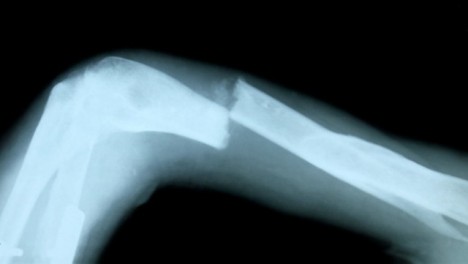

Mívá často zlomené kosti, aniž by si byla vědoma toho, jak ke zlomeninám přišla. Zranění se navíc dlouho hojí, protože u všech lidí se zvýšeným prahem bolesti dochází ke slabosti svalů a pomalejšímu hojení.